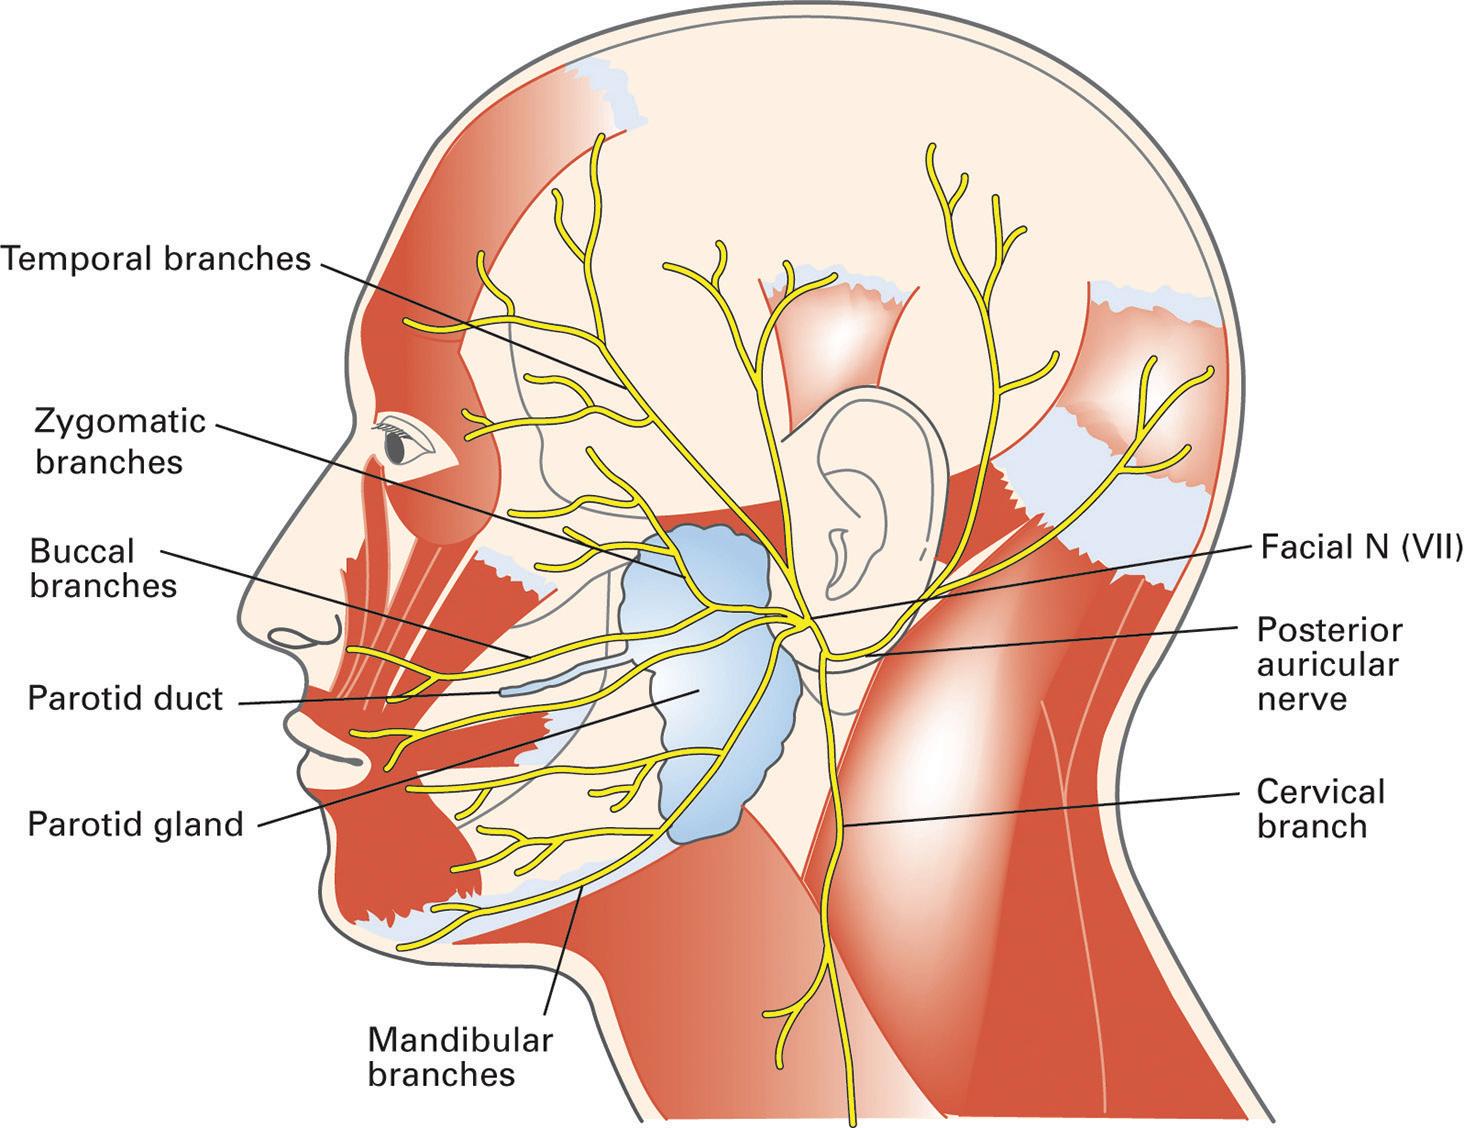

These facial muscles receive neural input from the facial nerve, also known as cranial nerve VII (Figure 1–2). Patients suffering from paralysis of the facial nerve, such as in Bell’s palsy, will experience problems during the preparatory phase of swallowing, characterized by difficulty maintaining a bolus in the oral cavity and lateral pooling of the bolus between the mandible and the cheek on the side of the palsy.

ANATOMY AND PHYSIOLOGY

the tongue, the pharynx, as a whole, elevates and then contracts to create a descending peristaltic wave behind the bolus. Elevation of the pharynx occurs when the paired palatopharyngeus and stylopharyngeus muscles contract. The walls of the pharyngeal chamber stiffen because of the sequential contraction of its three constrictors. The palatopharyngeus muscles and the pharyngeal constrictors are innervated by branches of cranial nerve X and the stylopharyngeus by cranial nerve IX, both via the pharyngeal plexus (see Figure 1–6).